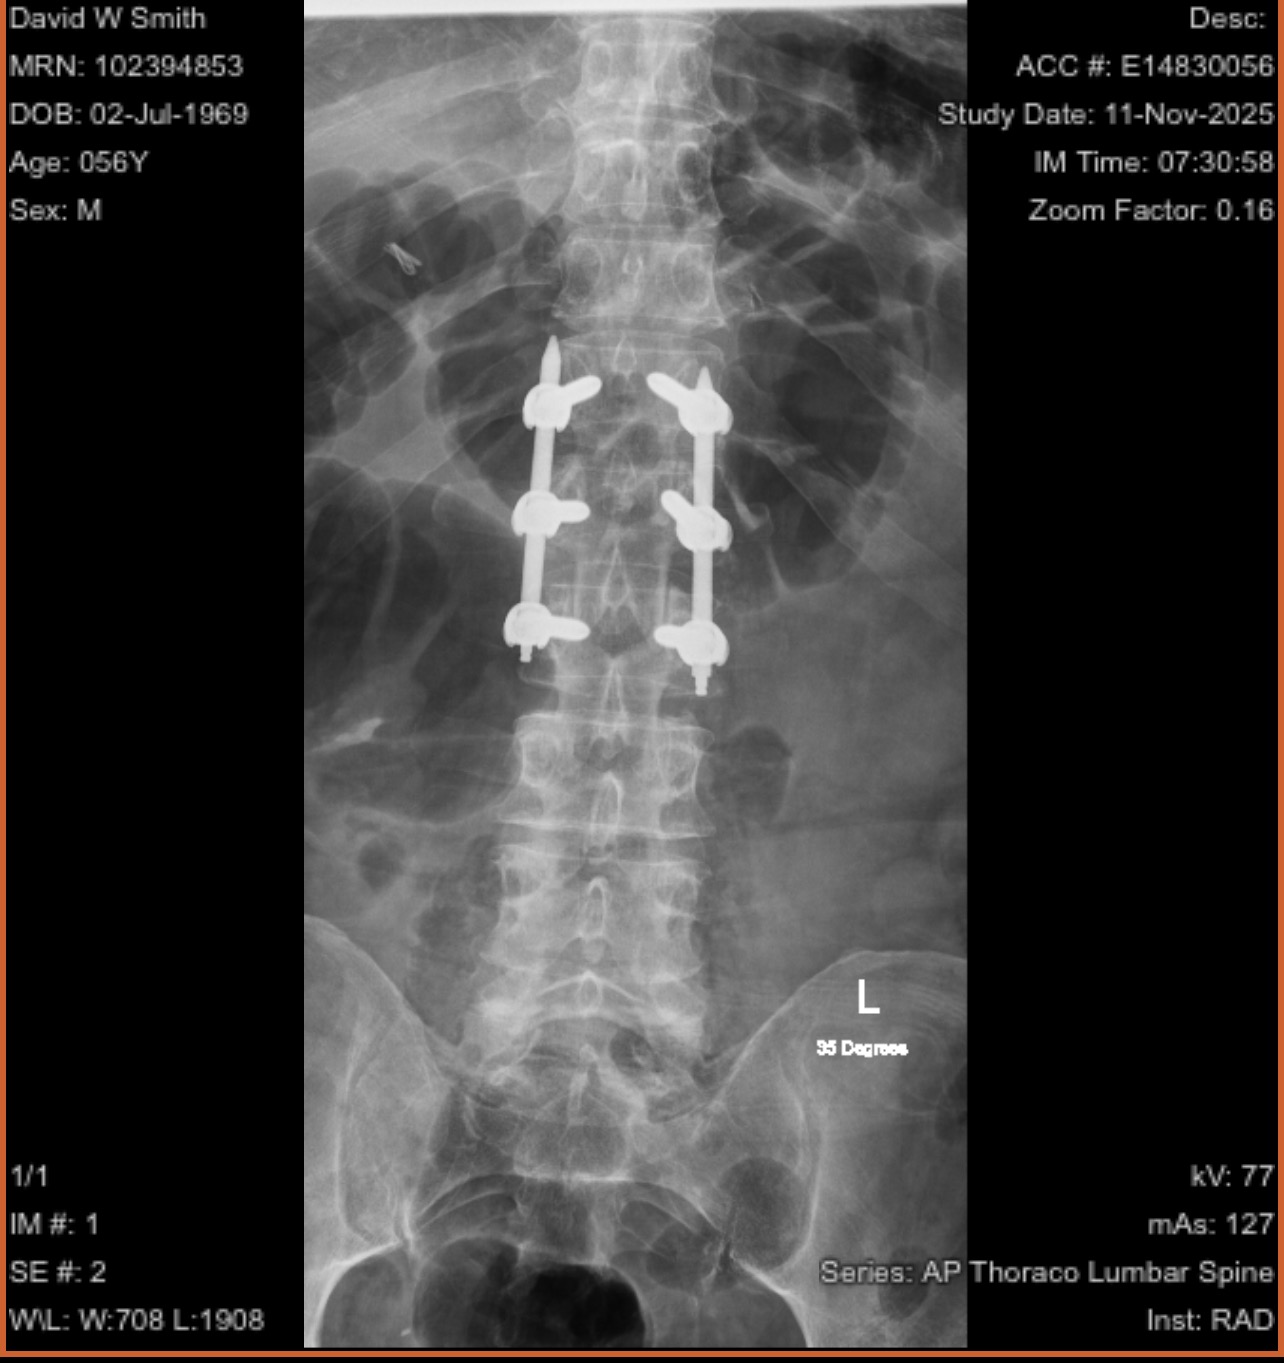

Hi everyone, my name is David, and I truly appreciate you taking a moment to read my story. A few days ago, I experienced a life-changing accident while working in the attic area above my garage. The floor gave way beneath me, and I fell through, resulting in two fractures in my back, a broken wrist, and a deep laceration to my head. I was rushed to the hospital, where I underwent back surgery, received stitches, and had my wrist placed in a cast. I am incredibly grateful to be here and healing, but this accident has created a financial situation that I am struggling to manage.